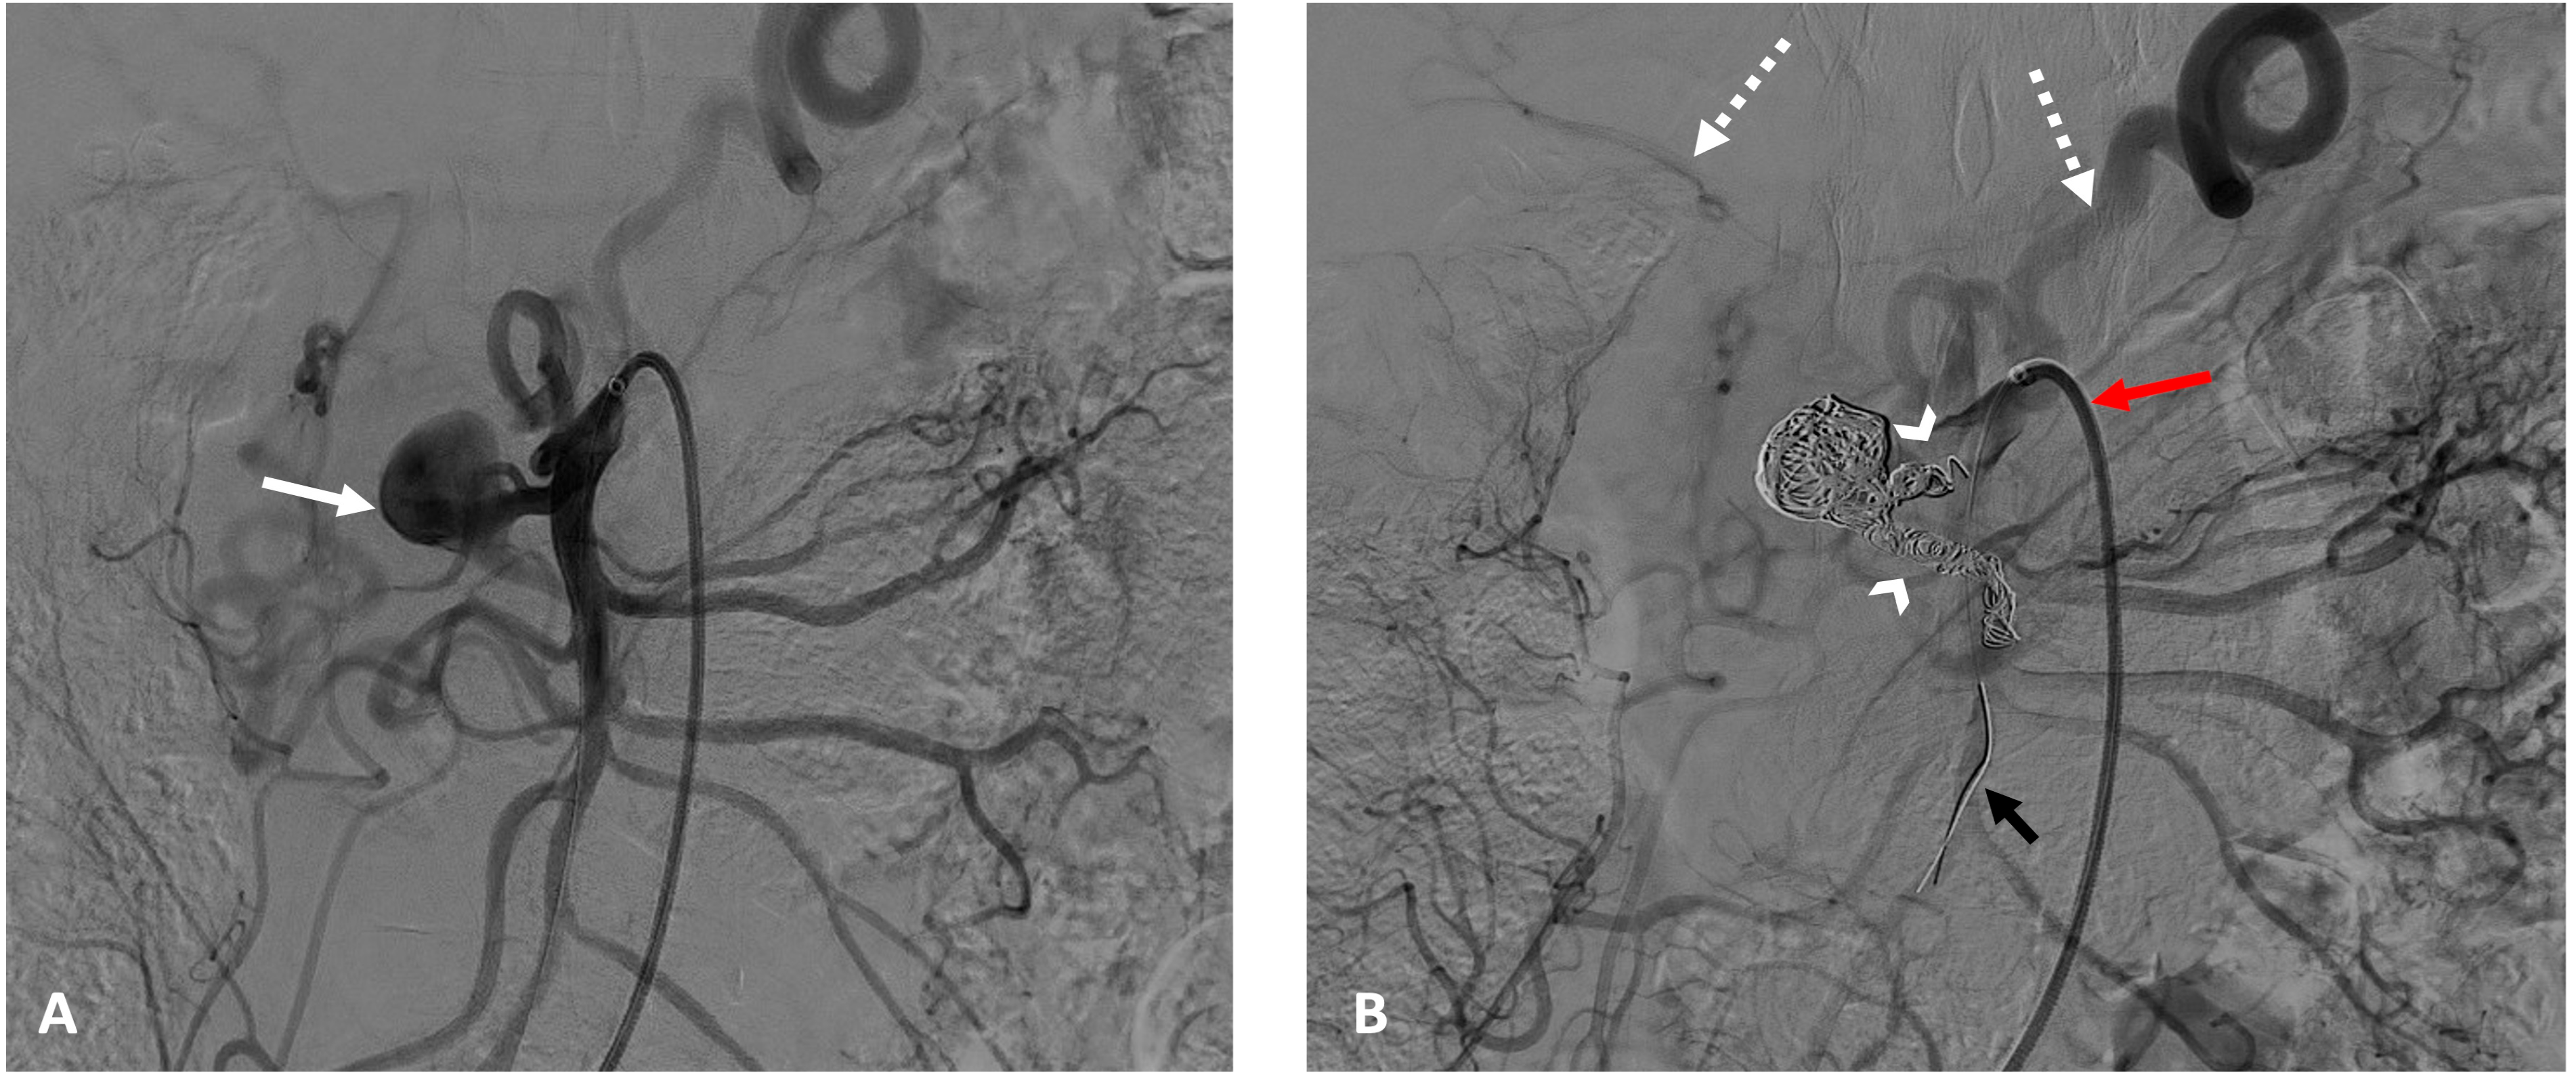

2.3. Embolization Interventions

3.2. Procedure Details

3.3. Technical and Clinical Success